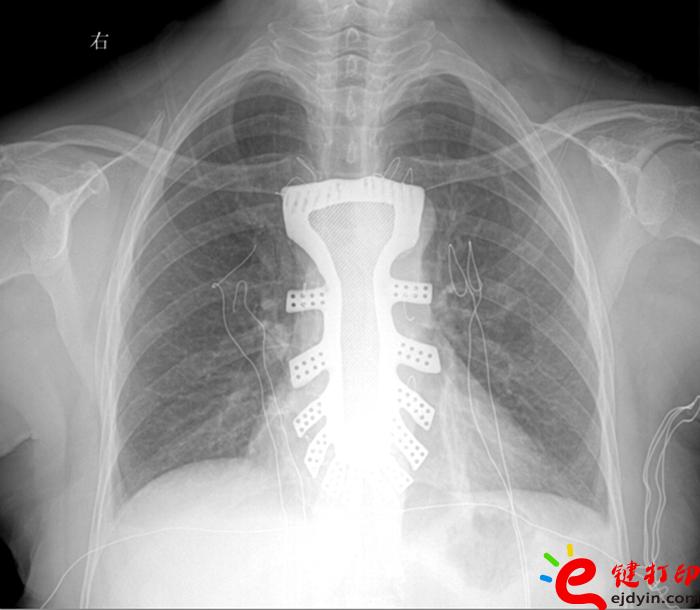

據王小平教授介紹,唐都醫院3D打印小組經過精密計算患者胸骨的大小、形狀等,充分研究討論,歷時一周,為患者設計出了手術使用的3D胸骨模型,并與西北工業大學凝固技術國家重點實驗室合作,為患者打印出了1:1鈦合金胸骨模型。隨后,又對該模型進行了一系列嚴密的醫學處理。

“手術歷時2.5小時,對患者的胸骨進行了整體切除,置換了鈦合金胸骨,目前患者恢復良好,未發現任何并發癥。”王小平教授稱,根據專業機構檢索,該手術是世界首例針對胸骨腫瘤疾病,將3D打印的可植入性鈦合金胸骨植入人體,實現病變胸骨的整體置換的手術。該手術的成功意味著未來將會為更多的胸骨腫瘤患者帶來福音。

參與此次3D鈦合金胸骨設計的唐都醫院3D打印團隊王臻博士表示,此次嘗試是3D打印技術與外科手術的一次完美結合。3D打印的個性化服務與醫學有著天然的聯系,目前3D打印技術在醫學上的研究越來越廣泛,為醫學的未來發展提供了無限可能。